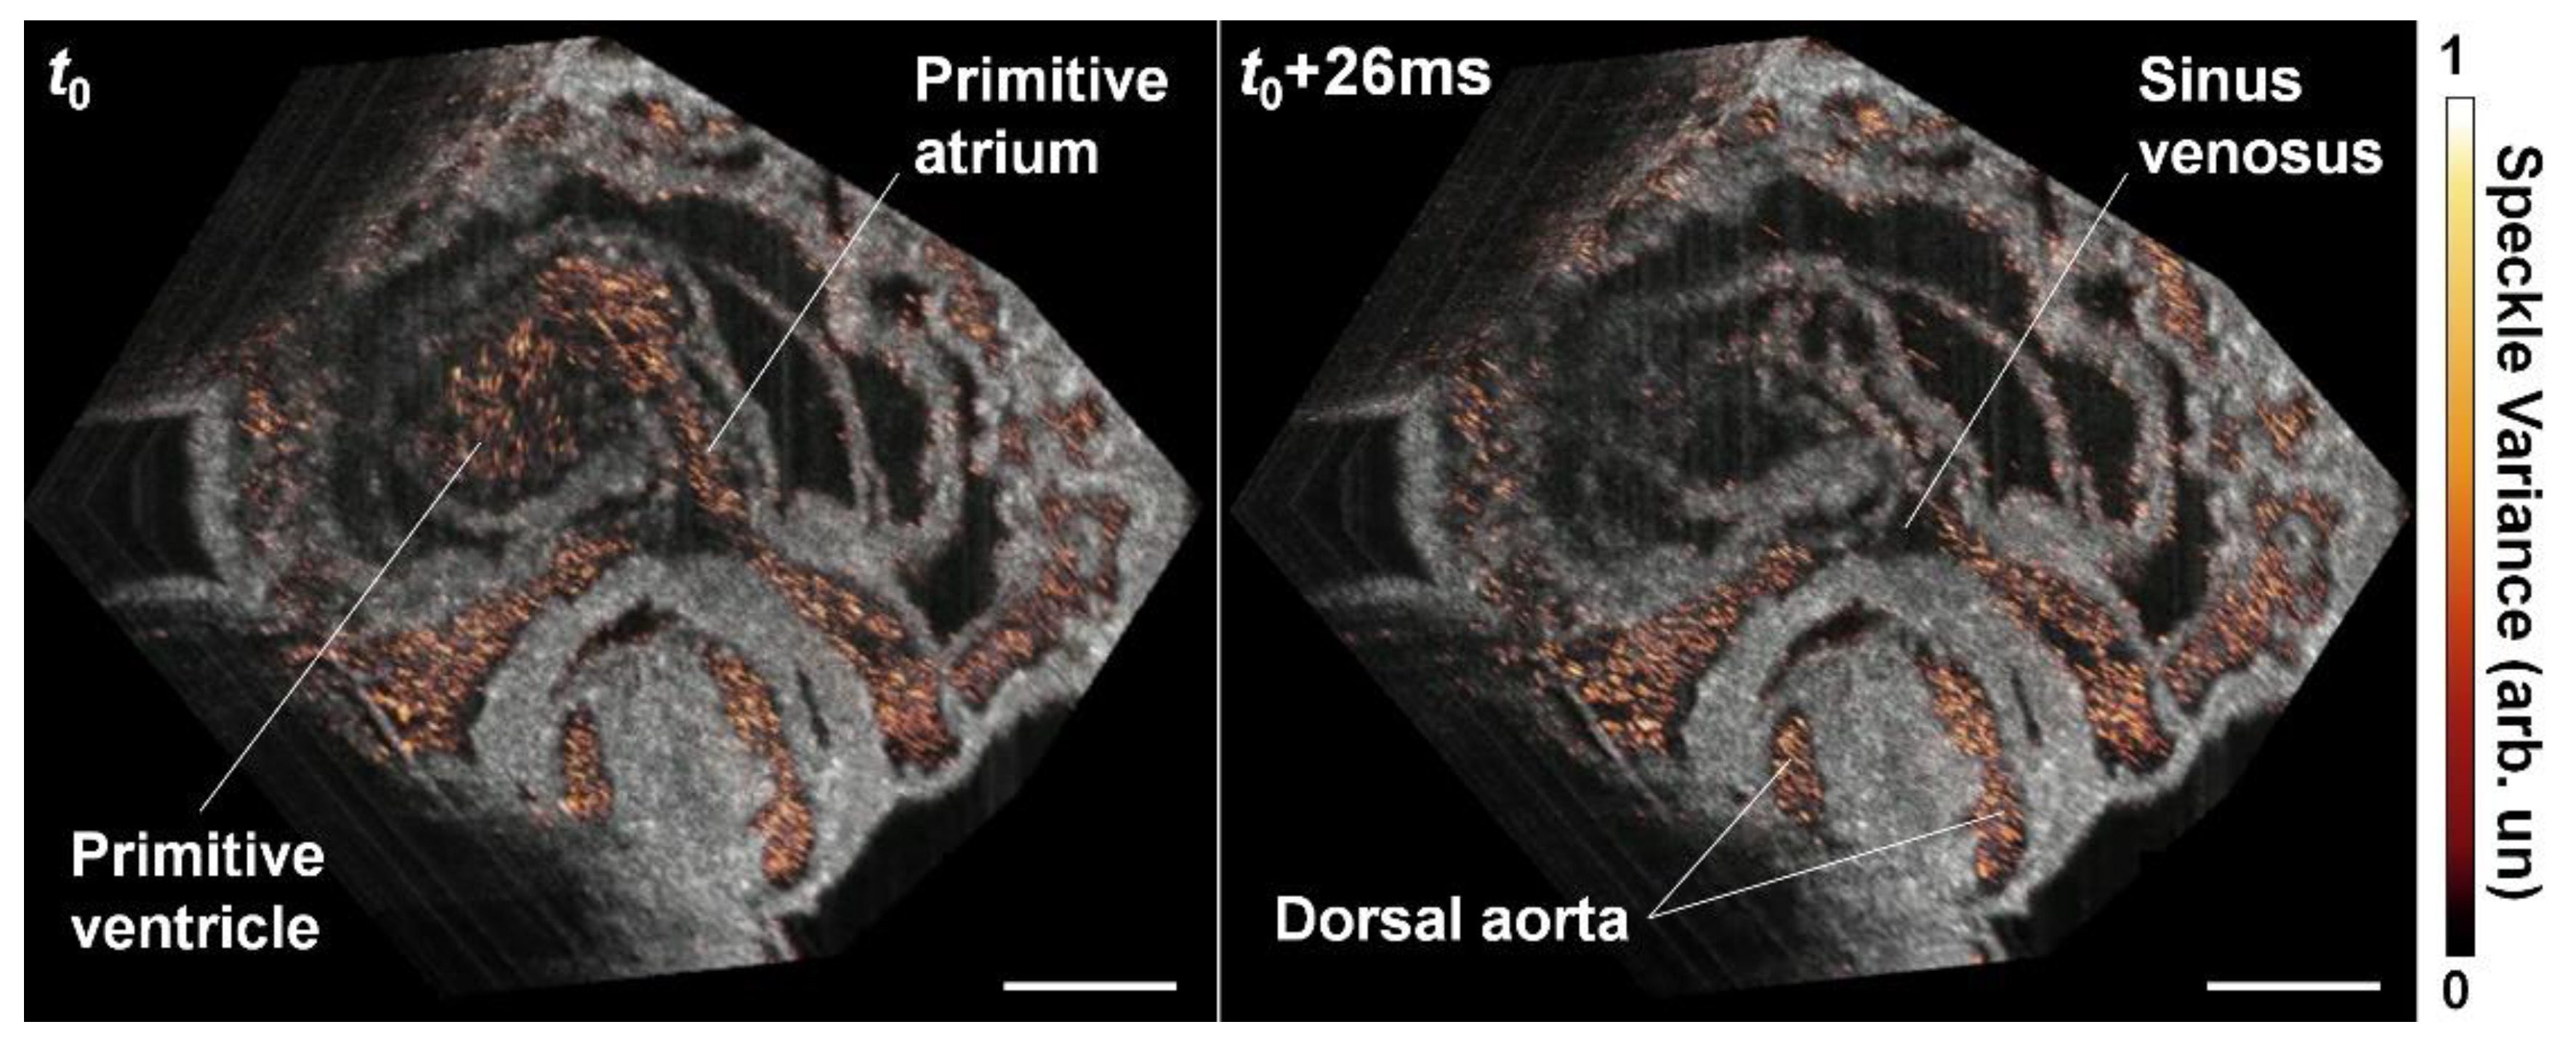

5. Hemodynamic Imaging with Doppler OCT

- Grishina, O.A.; Wang, S.; Larina, I.V. Speckle variance optical coherence tomography of blood flow in the beating mouse embryonic heart. J. Biophotonics 2017, 10, 735–743. [Google Scholar] [CrossRef]

- Wang, S.; Lakomy, D.S.; Garcia, M.D.; Lopez, A.L.; Larin, K.V.; Larina, I.V. Four-dimensional live imaging of hemodynamics in mammalian embryonic heart with Doppler optical coherence tomography. J. Biophotonics 2016, 9, 837–847. [Google Scholar] [CrossRef] [Green Version]

- Wang, S.; Larina, I.V. Live mechanistic assessment of localized cardiac pumping in mammalian tubular embryonic heart. J. Biomed. Opt. 2020, 25, 086001. [Google Scholar] [CrossRef]